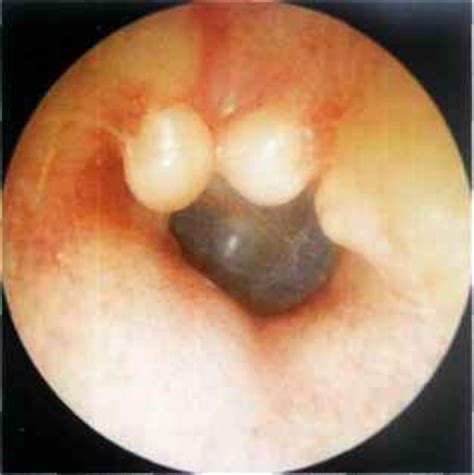

Exostose du conduit auditif

L’exostose correspond à la formation d’os dans le conduit auditif externe. C’est une réaction de défense de l’organisme contre une agression extérieure. Cette affection est la conséquence de l’agression de l’eau froide sur le conduit auditif externe. Les surfeurs mais aussi les kayakistes et les nageurs en eaux froides comme les triathlètes y sont sujets.

Les conséquences peuvent être graves. L’exostose peut en effet provoquer une mauvaise évacuation de l’eau entre la masse osseuse et le tympan. D’où un risque d’otites externes extrêmement douloureuses à répétition. Et à long terme, si rien n’est fait, les excroissances osseuses peuvent aller jusqu’à l’obturation complète et la perte d’audition.